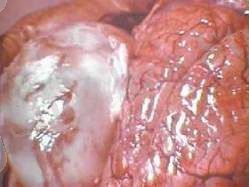

Эхинококпен зақымданған бауыр

Дене тұрқы 3-5 мм, бас пен 3-4 бөліктен тұрады. . Басында 4 сорғышы, 35-40 ілмешектері болады. Негізгі йесі қасқыр немесе ит. Аралық йесі үй жануарлары немесе адам болу мүмкін. Бауырды, өкпені, бүйректі, кейде миды зақымдайды.

Зақымданған бауыр бірнеше есе ұлғаяды. УДЗ, рентген арқылы анықталады. Тек ота жасау арқылы емделеді.